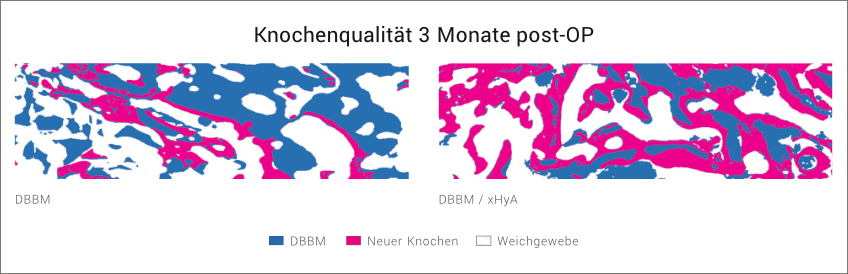

Diese Beobachtung wurde auch in einem Split- Mouth Case erhalten, in dem Extraktionsalveolen entweder mit einem langsam resorbierbaren Knochenersatzmaterial (DBBM) alleine oder mit einer Kombination aus DBBM/xHyA aufgefüllt wurden.

Nach 3 Monaten waren in der xHyA-Gruppe deutlich mehr neu gebildeter Knochen und deutlich weniger Restpartikel des avitalen Knochenersatzmaterials vorhanden.27